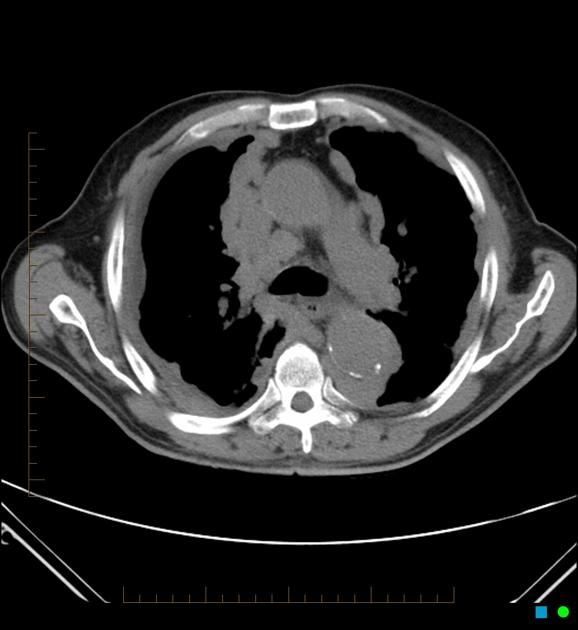

② 胸部CT検査

胸部X線検査で異常が認められた場合や、より詳細な評価が必要な場合に実施されます。CT検査は、胸膜の肥厚の範囲、厚さ、石灰化の有無、肺実質への影響などを三次元的に詳細に把握することができます。アスベスト関連の胸膜肥厚では、壁側胸膜に沿った肥厚や、特徴的な石灰化像が確認されることがあります。

出典:Radiopaedia.org(2025)「Pleural thickening」https://radiopaedia.org/articles/pleural-thickening